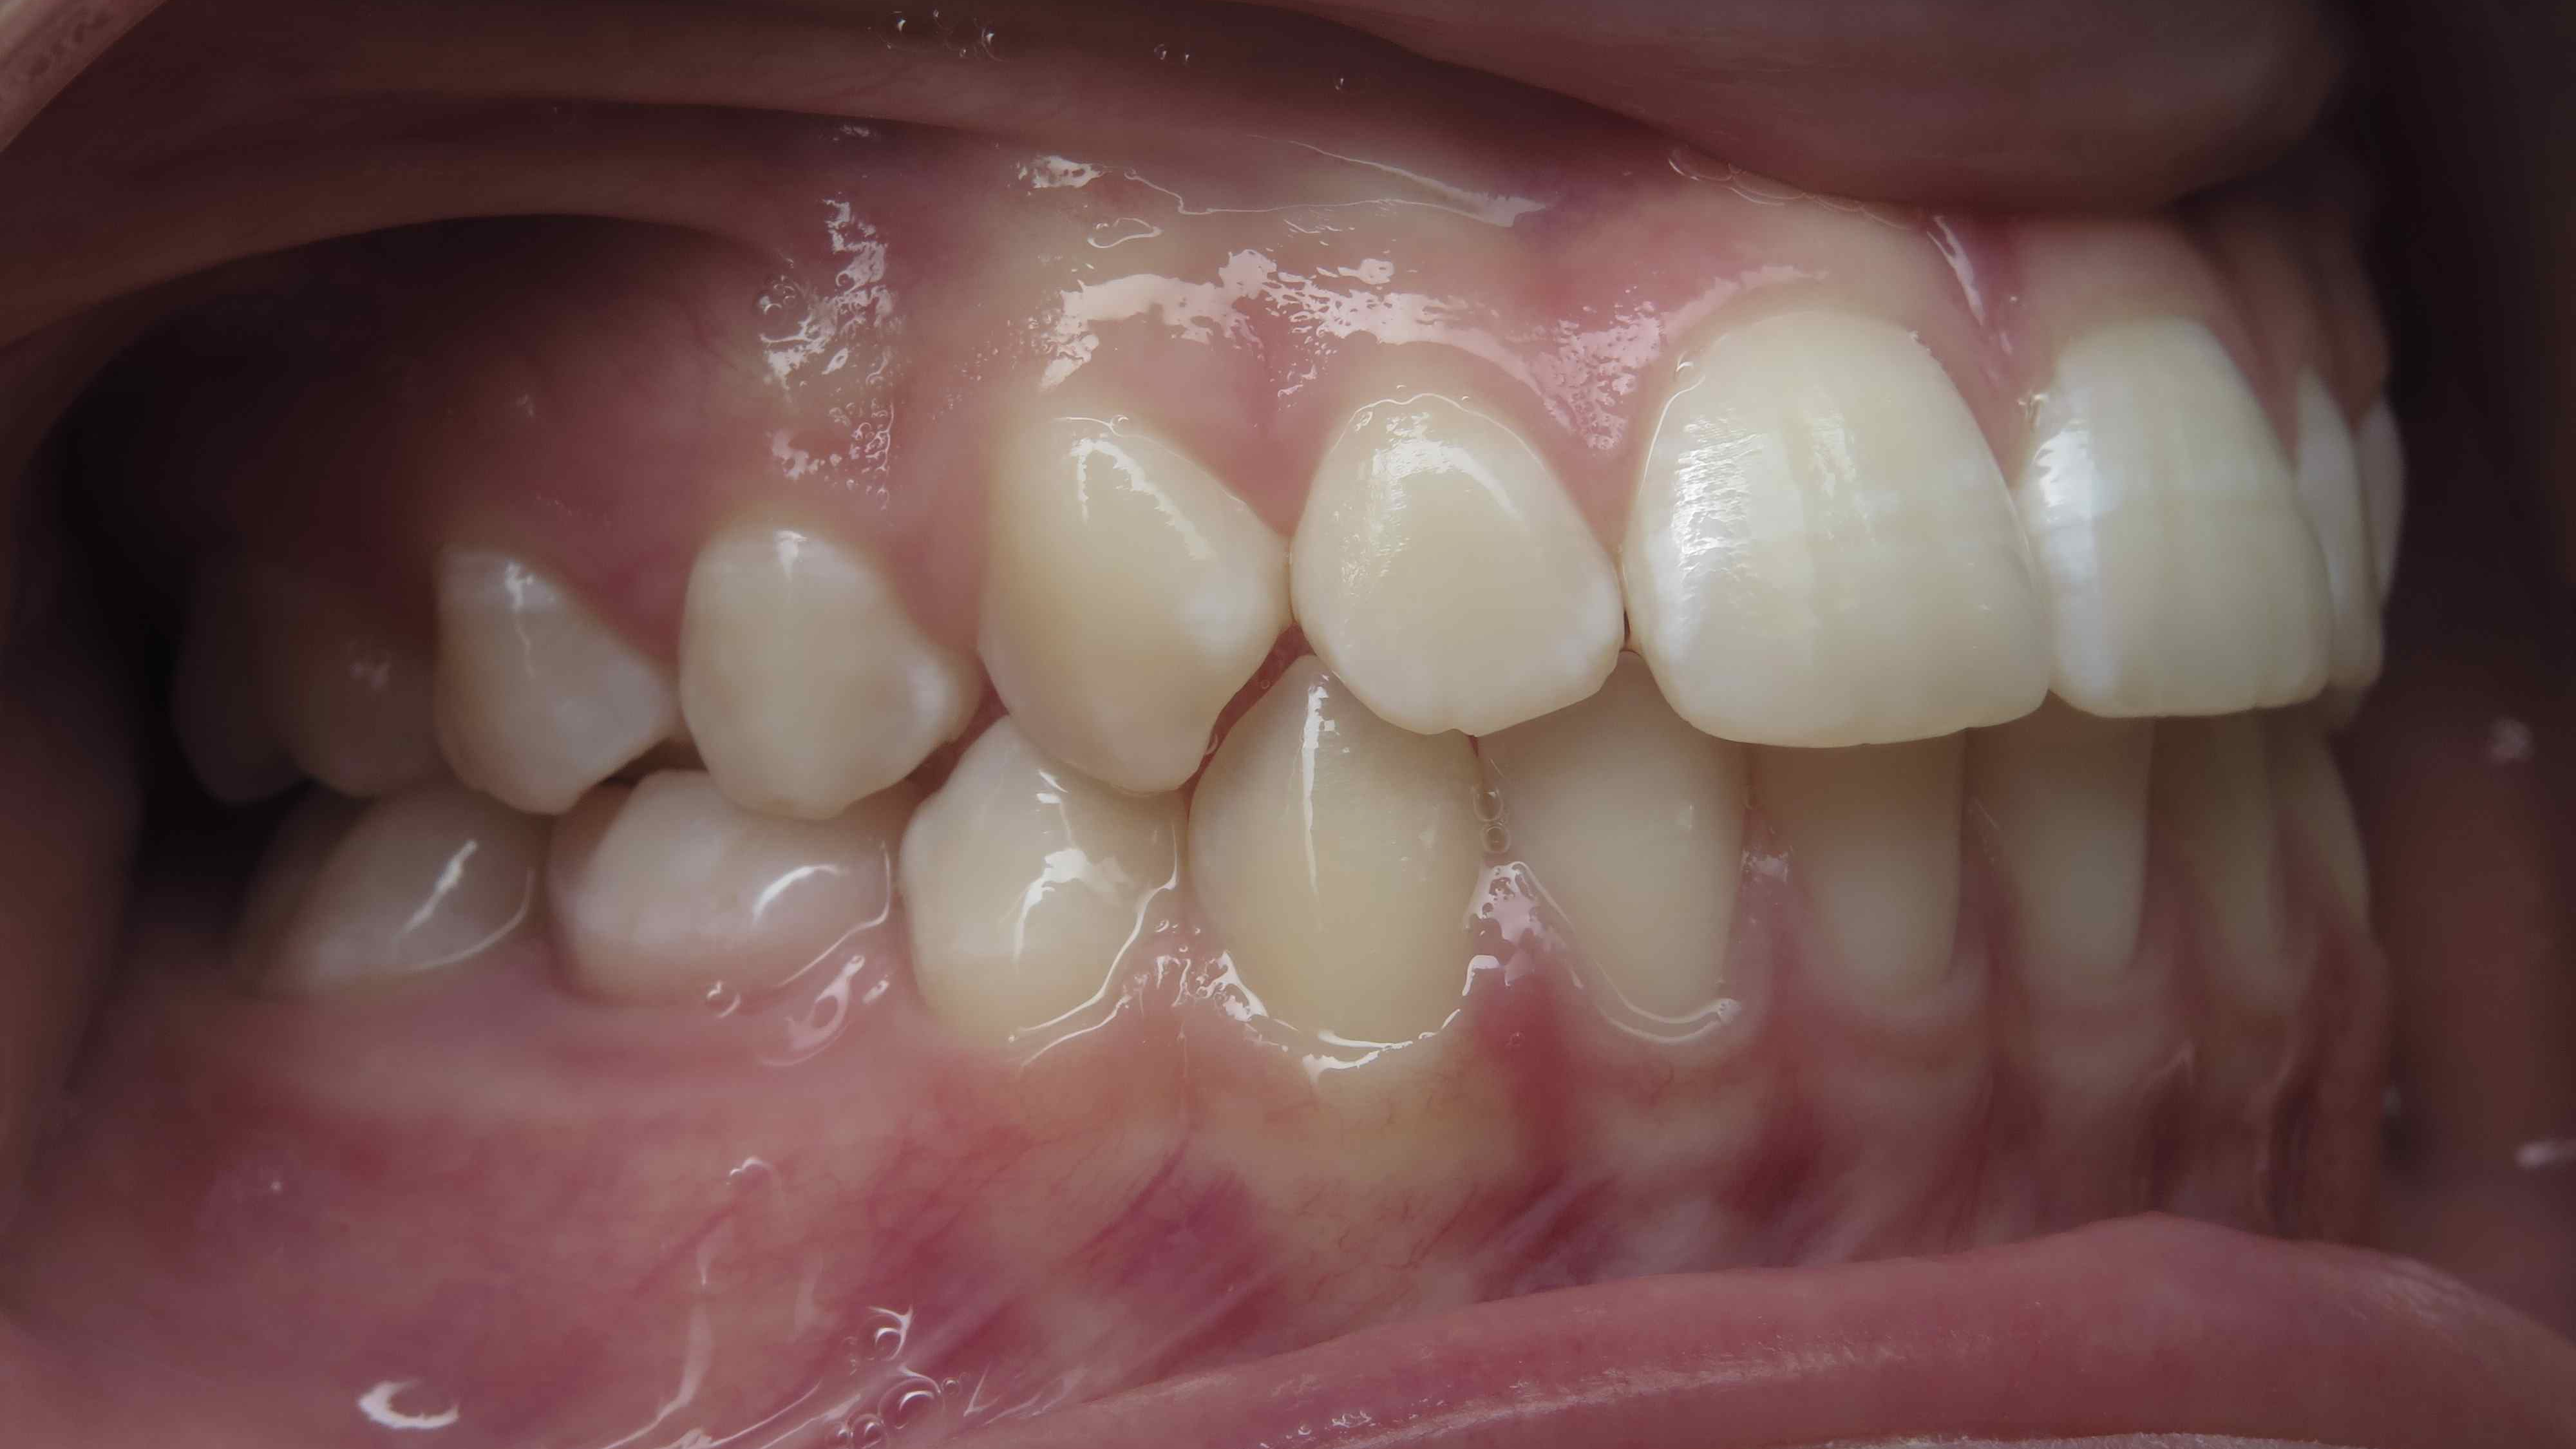

appareillage mobile pendant 35 mois

surveillance évolution de la dentition pendant 5 ans

appareillage multibagues traitement en cours

bilan début et en cours de traitement